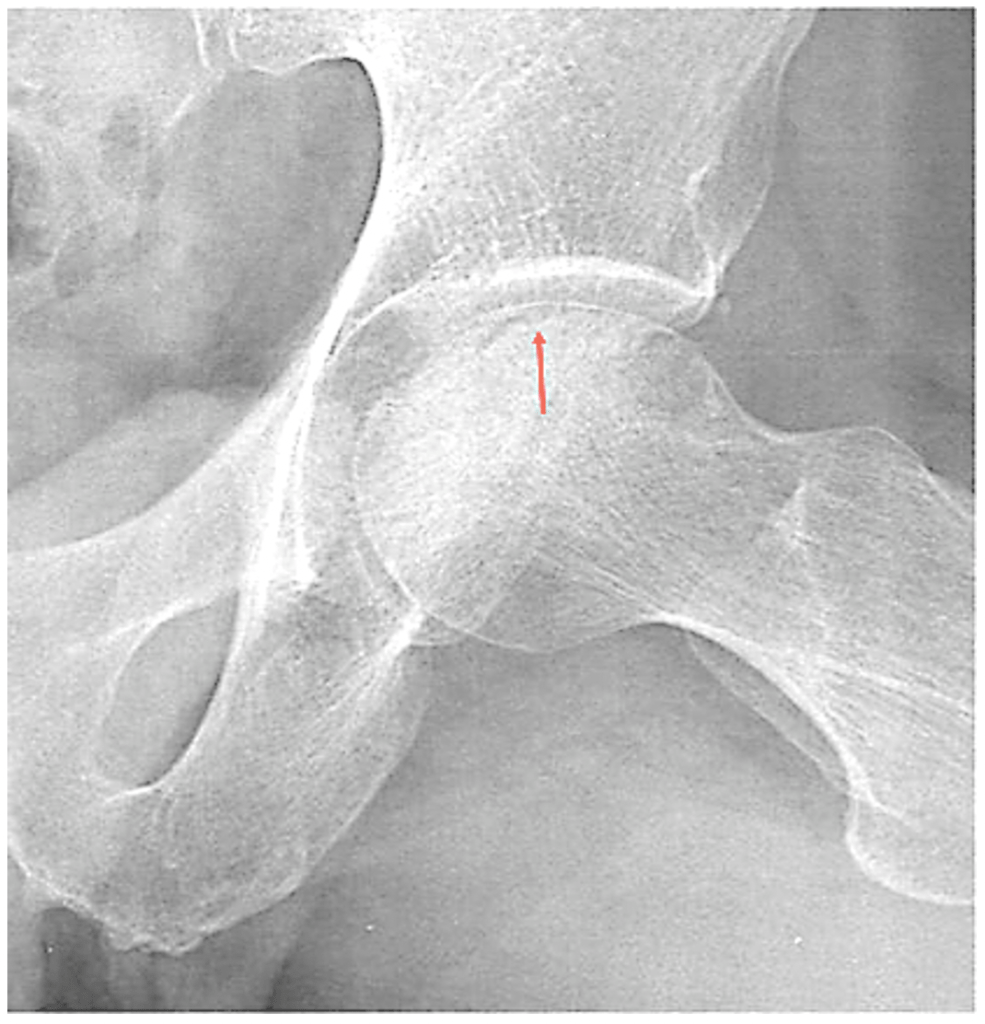

From radiopaedia.org

LeggCalvéPerthes disease Image Legg Calve Disease It occurs when the blood supply to the femur bone. Learn about the diagnosis and treatment of perthes disease, a condition that affects the hip joint in children. Without an adequate blood supply, the bone cells die, a process called avascular necrosis. It can cause hip pain, stiffness, and limp, and may. It occurs when the blood supply to the. Legg Calve Disease.